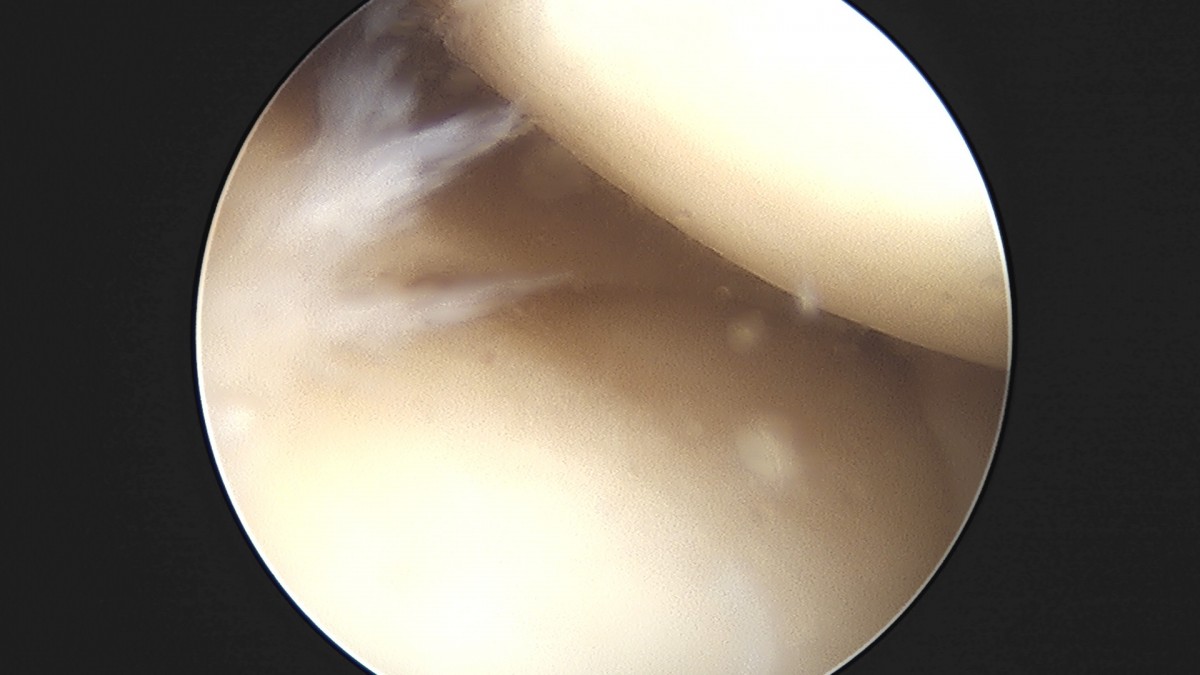

이재상원장님 무릎 반월상 연골판 절제술 조미O 환자

작성자 최고관리자 댓글 0건 조회 368회 작성일 25-09-16 16:01